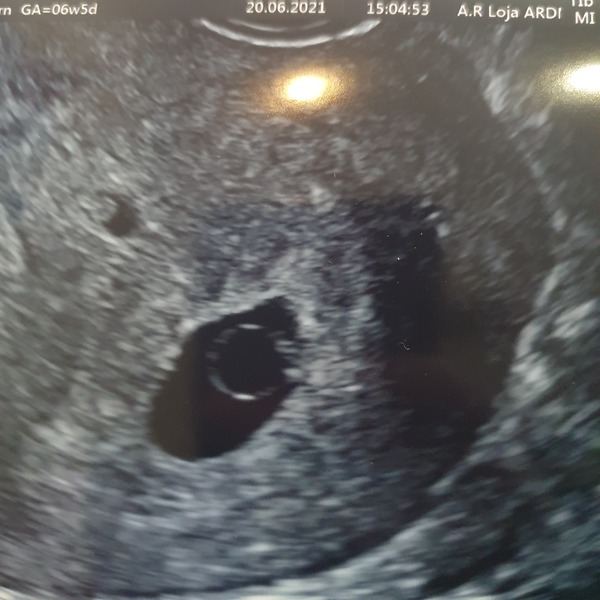

I went for an early reassurance scan at what should have been 6 weeks and 4 days. The sonographer wished me congratulations as if all was good. It was only when I commented on the size of the yolk sac that she agreed it was very large and it would be a waiting game to see if the pregnancy would progress. She recommended another scan in 10 days time. After googling large yolk sac I'm not holding out much hope for a good outcome. Especially with the lack of my usual pregnancy symptoms.

Next scan is the coming Monday. Presently time is at a standstill. I really hope it doesn't drag out as we are hitting the summer holidays and facing a miscarriage with all my kids off school is not an exciting prospect. Any one had any experience with a large yolk sac at this early stage?